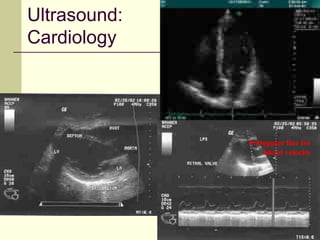

Ultrasound:

Cardiology

Doppler line for

blood velocity